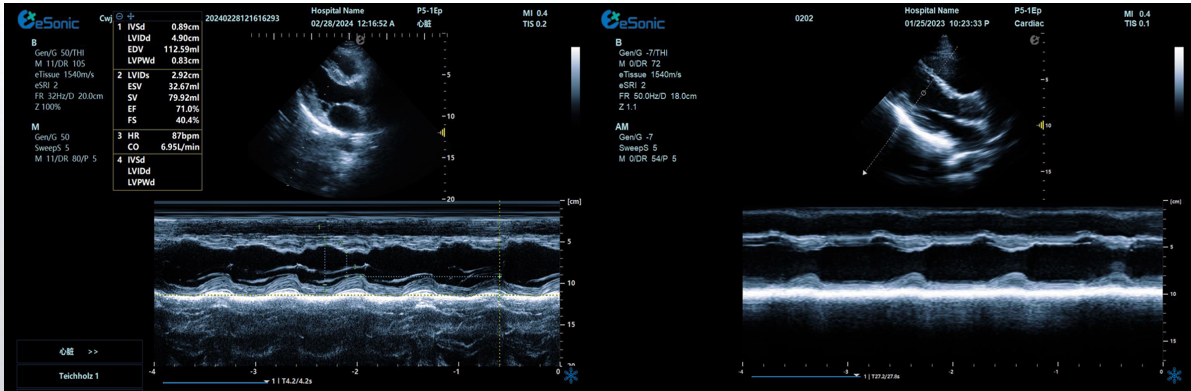

临床病例(一)

女性,68岁,临床诊断:冠心病

超声表现:左房大,左室壁运动幅度明显减低,以室间隔较明显;心包腔内见无回声区,右室前壁8mm,左室侧壁10mm。

冠心病、心包积液

相关心脏应用功能--M型、解剖M型

M型-最常用的心功能检测法;高血压病除二维观察外,其室壁增厚及心腔大小的改变,均也可通过M型测量而获得

解剖M型-适用于心尖上翘者、瘦长体形者、室壁瘤形成等...

相关心脏应用功能--M型、解剖M型技术总结:

1edf4ffc259114ab6502340e160add1.pngM型超声是评估心脏功能的重要方法之一,通过其高速的取样帧频,可以将心脏各个阶段的运动状态显示出来。

解剖m型:

不受角度限制,打破技术壁垒不影响M型图谱分辨率。

三线解剖M型:

同一心动周期,多节段评估心功能。

解决节段运动异常和判断同步化运动。

彩色M型:

直观显示室璧运动和血流动力学关系。

更精准判断血流时向,更精准评估心脏功能。